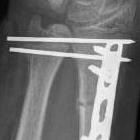

Shortening of radius with disruption of DRUJ on lateral

Widening of interval between radius and ulna / clear disruption of DRUJ

Concern for disruption of DRUJ on lateral

Radius ORIF with dynamic compression plates